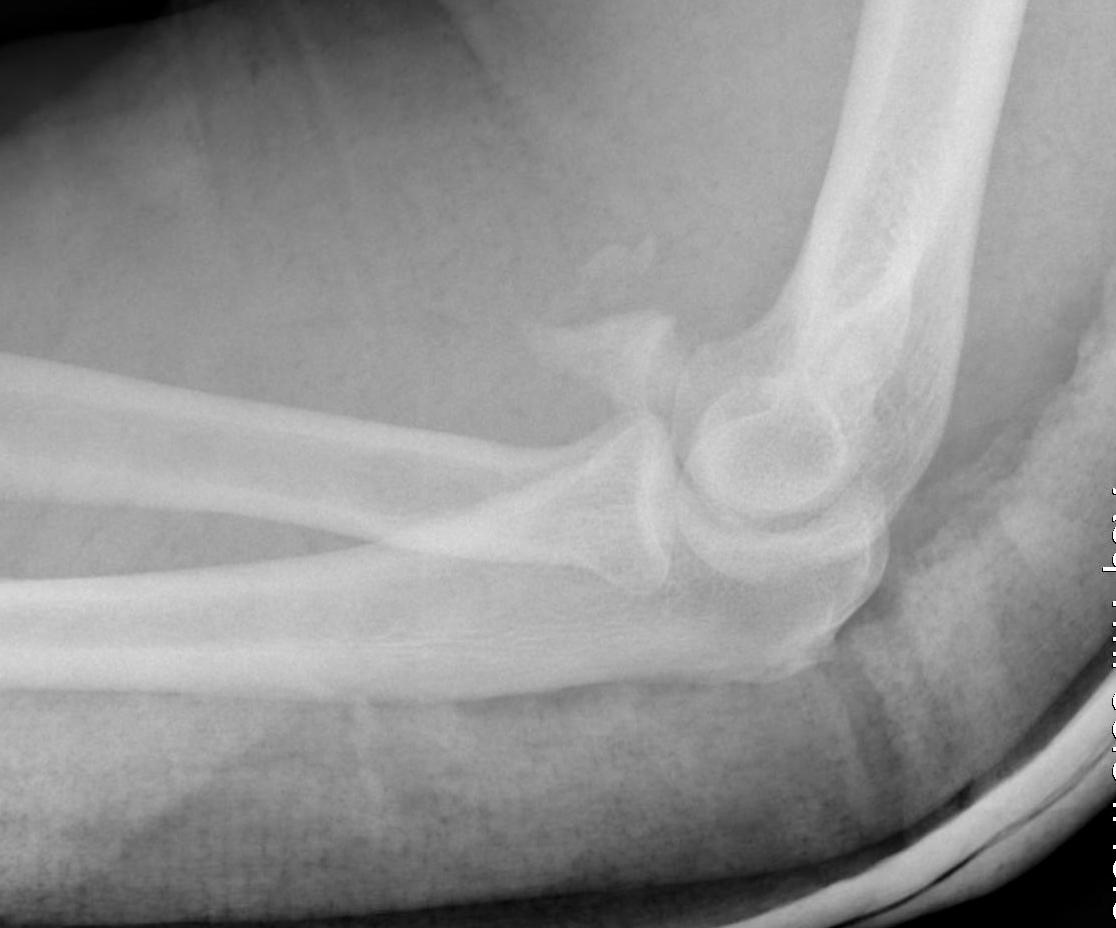

Regan and Morrey classification of transverse coronoid fractures

Elbow stability related to size of coronoid fragment

| Type I | Type II | Type II |

|---|---|---|

| Small coronoid process fracture | 50% of coronoid process | > 50% coronoid process |

| Usually stable |

Capsular attachment Elbow unstable |

Capsule + MCL attachment Elbow unstable

|